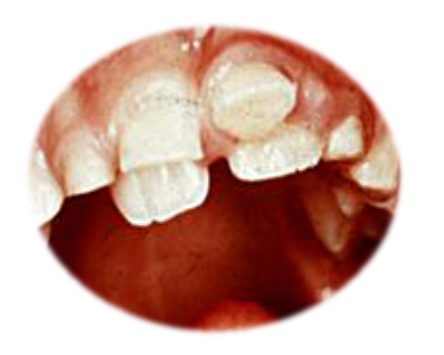

Slika 1. Napravilno nicanje donjih stalnih sekutića iza mlečnih predhodnika(A) često je znak da nema dovoljno mesta u vlilicama(veliki zubi, male vilice) i da može da nastane nepravilnost u postavci koja se naziva teskoba(B)

Čim se primeti da se stalni zubi pojavljuju iza mlečnih sekutiča, koji su minimalno rasklaćeni, potrebno je da se hitno javite dečjem stomatologu.(slika 1A) Neophodna je procena veličine stalnih zuba i postojećeg prostora i na osnovu toga odlučuje da li da se mlečni prvi sekutići odmah izvade, ali često i drugi, ili da se sačeka još malo. Značajno je i da li su mlečni zubi počeli da se klate ili ne. Sledi će najverovatnije i nošenje proteze za ispravljanje zuba(ortodontski aparat), koje imaju za cilj da prošire vilicu i obezbede prostor za smestaj zuba. Ako se na vreme reaguje i podstiče rast vilica moće da se izbegne(ali ne uvek) složenija terapija. Ako se zakasni(to znači više godina) i nista ne preduzme, dok se ne postave i bočni stalni zub, često je jedino rešenje vađenje zdravih stalnih zuba(najčešće prvi premolar ili popularno “stalna četvorka”) kako bi se obezbedio prostor za smeštaj svih zuba.